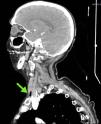

This is the case of a hospitalized patient whose jugular central catheter is removed while sitting on a couch prior to his hospitalization. A few seconds later, the patient develops dissociative disorder, hypokinesia, and acute respiratory failure. A stroke is suspected. The simple cranial CT scan and coronary computed tomography angiography (CCTA) performed reveal no signs of acute ischemia or major cerebral vessel occlusion, but the presence of numerous aerial bubbles at right jugular vein, cerebral cavernous sinuses, extra-axial intracranial sinuses, and a few intra-medulla oblongata bubbles at clivus level (Figs. 1–3). All signs of venous air embolism. This is a rare complication associated with central venous catheters. However, proper management of these is important regarding insertion, maintenance, and removal both at the intensive care unit and hospital ward settings to avoid complications.